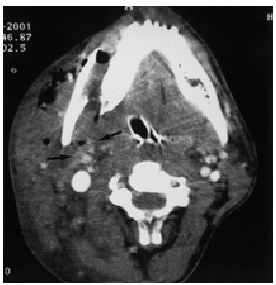

Se realizó una TC facial y cervical con contraste intravenoso (i.v.) apreciándose una fractura de la porción horizontal de la rama mandibular derecha con gran desplazamiento lateral y gran hematoma que ocupaba la parte lateral derecha del cuello. Llamaba la atención la pérdida de nitidez de los vasos en las ramas carotídeas derechas, estando nítida la vena yugular homolateral (fig. 1). Con estos hallazgos se sospechó una afección carotídea realizándose una arteriografía que permitió visualizar un aneurisma postraumático a 4 cm del origen de la carótida interna derecha (fig. 2) y la sección de una rama distal de la arteria mandibular con fuga de contraste. Se procedió a embolización de ambas ramas, con buen resultado.

Figura 1. TC cervical con contraste: se observa una pérdida de nitidez vascular en las ramas carotídeas derechas.